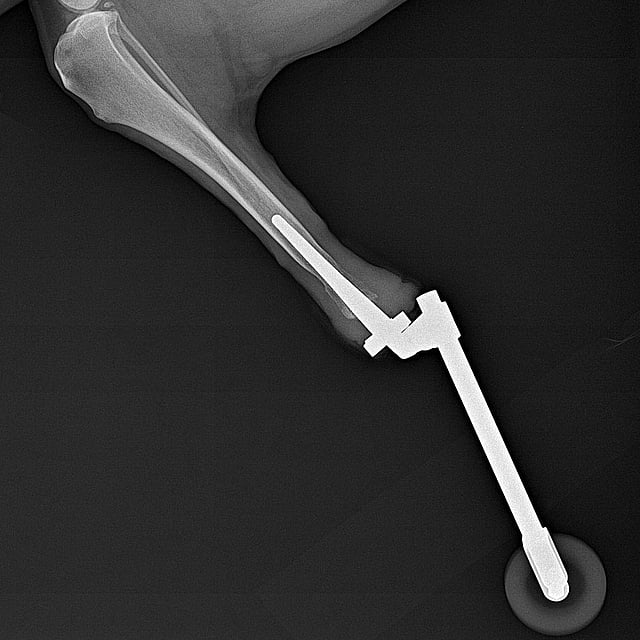

Prothèse ITAP, une nouvelle chance de mobilité

La prothèse ITAP (Intraosseous Transcutaneous Amputation Prosthesis) est une innovation chirurgicale conçue pour redonner une mobilité naturelle aux animaux ayant subi une amputation partielle d’un membre.

Contrairement aux prothèses classiques à emboîture (qui s’ajustent autour du moignon), l’ITAP est directement ancrée dans l’os, comme une racine, et traverse la peau de manière permanente. Cela permet de fixer une prothèse externe légère, stable et confortable.

Le système ITAP s’appuie sur un processus appelé ostéointégration : l’os se fixe naturellement à la surface de l’implant, créant une continuité mécanique entre le squelette et la prothèse.